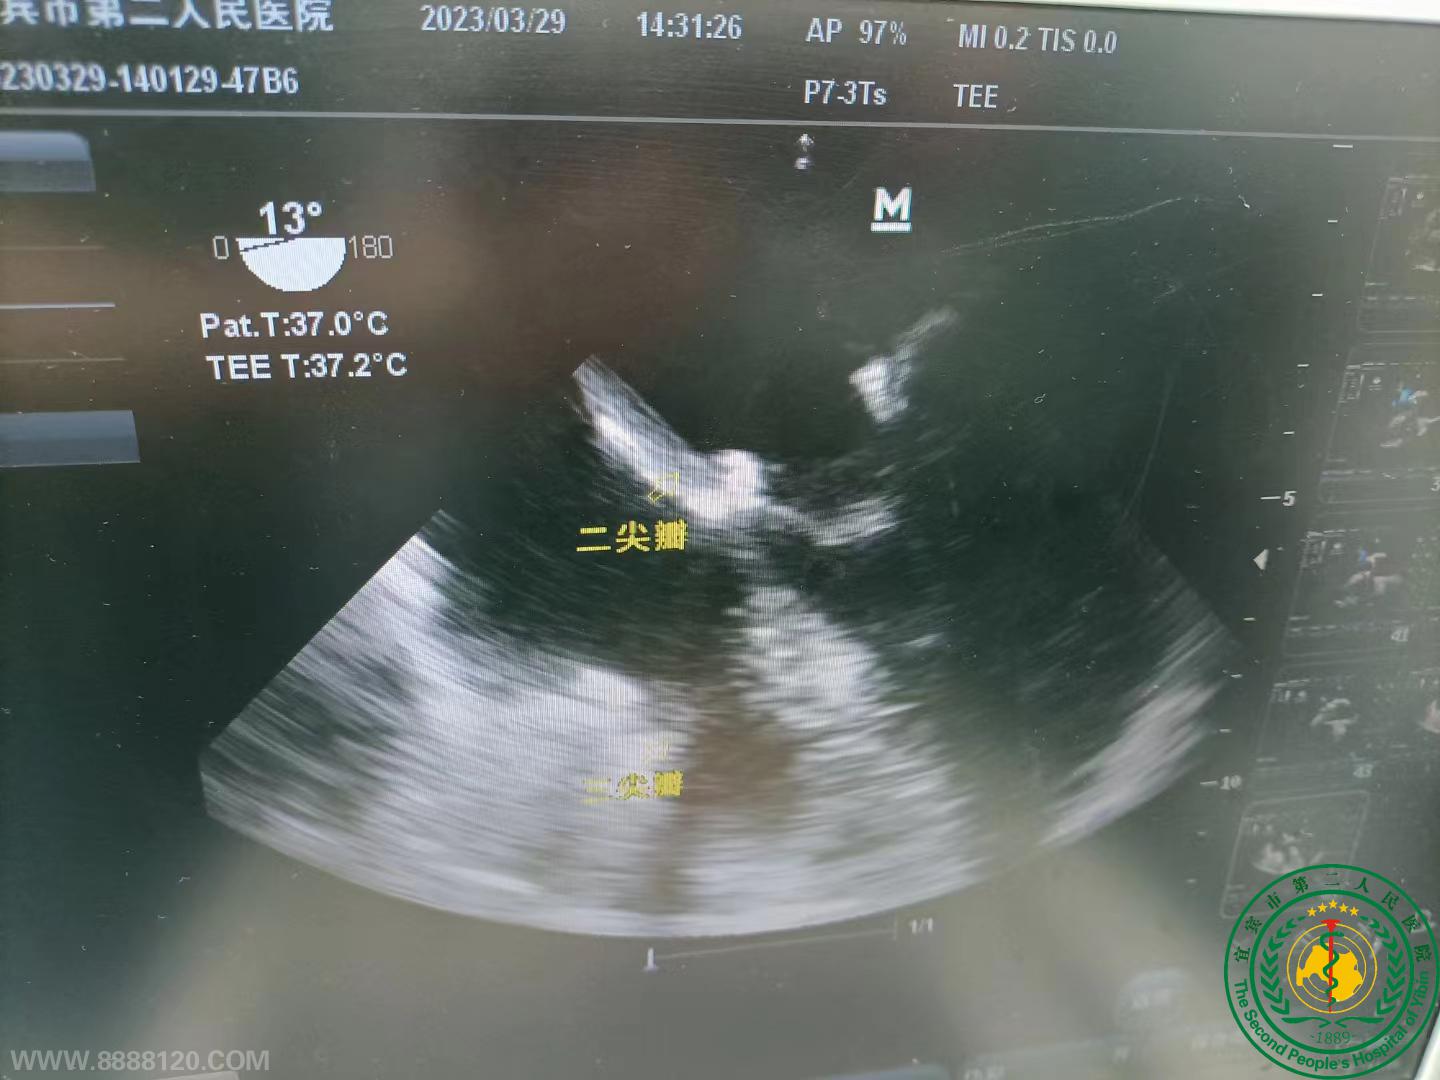

宜宾首例自主二尖瓣人工瓣环成形同期主动脉瓣置换及三尖瓣成形手术在我院成功开展

宜宾首例自主二尖瓣人工瓣环成形同期主动脉瓣置换及三尖瓣成形手术在我院成功开展48727